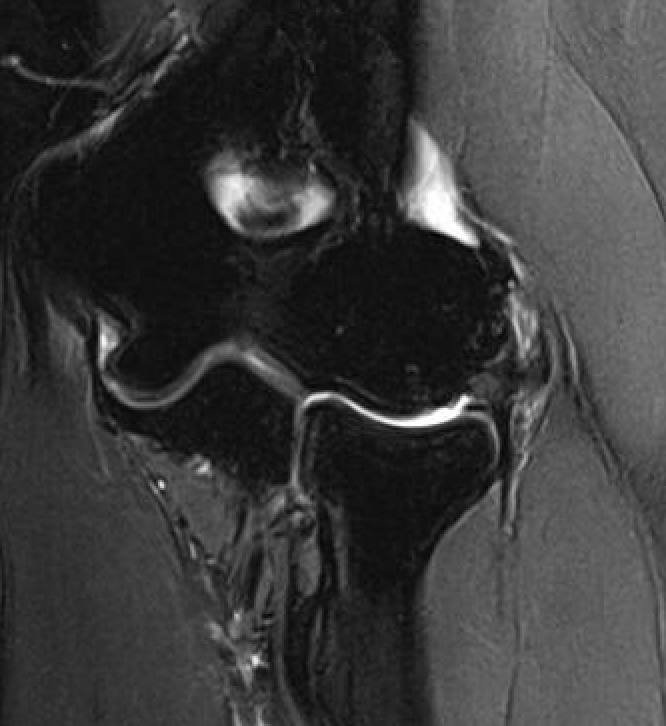

MRI

High grade partial tears of ECRB on lateral eipcondyle

Tendonopathy of the common extensor origin, with thickening and high grade tear partial tear

Tendonopathy of the common extensor origin, with thickening and high grade tear partial tear